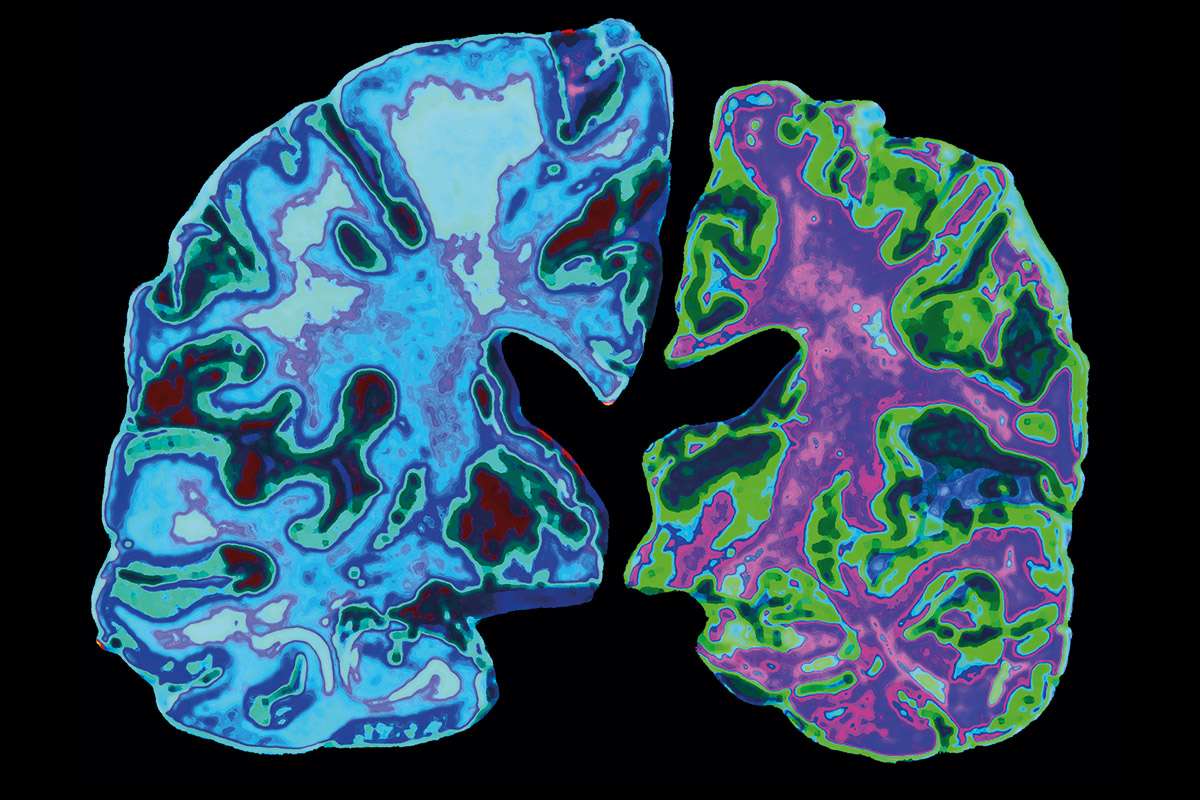

“These antibodies seem to have cleared (out) pathological tau. Pathological tau is one of the components of these tangles that we find in the brains of patients with Alzheimers disease,” she explained. The response lasted for months, according to UNM.

Those long tangles “disrupt the ability of neurons to communicate with one another,” the school points out, adding that tau is “normally a stabilizing structure inside of neurons.”